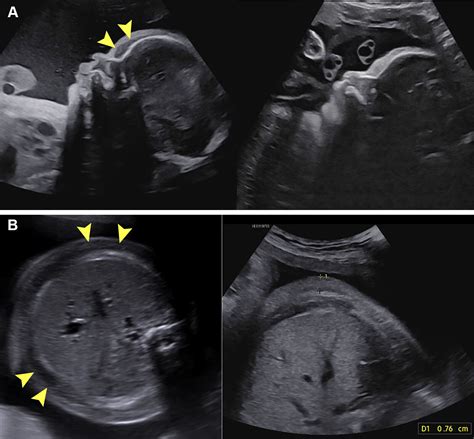

• Swelling: Visible swelling in the fetus, particularly in the extremities, abdomen, or face.

• Abnormal Ultrasound Findings: Ultrasound examinations may reveal fluid accumulation in the fetal tissues or body cavities.

• Ultrasound: Ultrasound examinations are the most common method for detecting fetal edema. They can reveal fluid accumulation in the fetal tissues and body cavities.